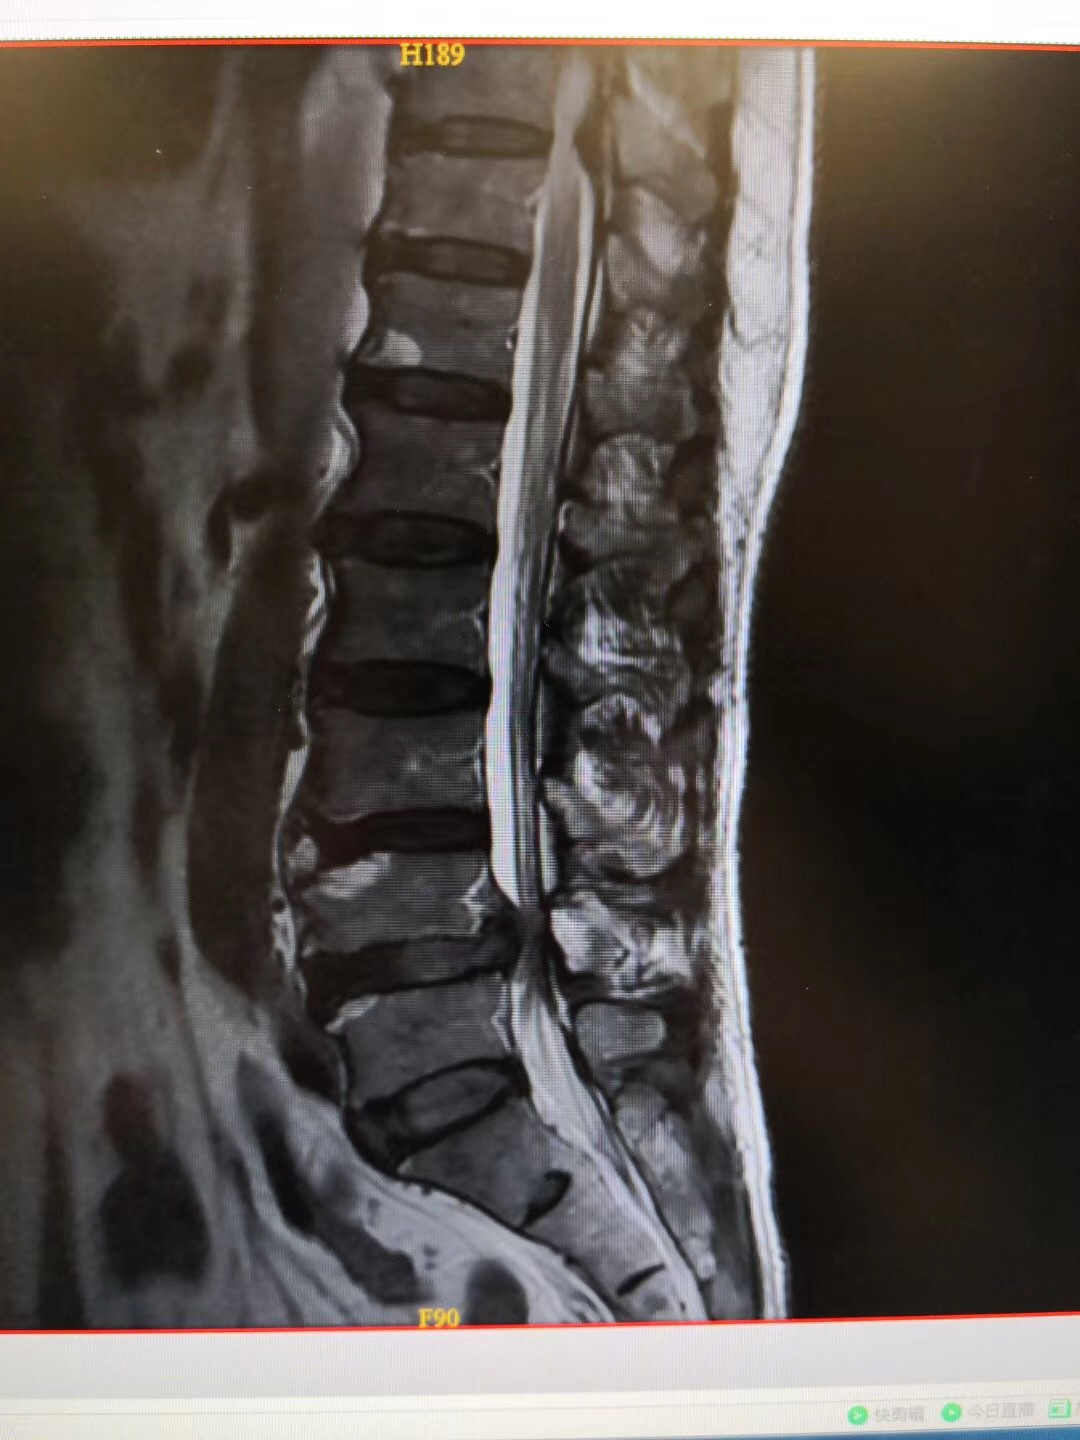

患者:65岁男性,广东湛江籍。

症状:双下肢麻痛伴间歇性跛行1年,行走100米即出现双下肢麻痛,严重影响生活。

诊断:腰椎间盘突出伴椎管狭窄症(L4/5节段),腰椎不稳定(L4/5节段),予施行“后路腰椎管减压固定融合术”治疗。

术后:术后第二天患者即可腰围保护下床行走活动,双下肢麻痛基本缓解,效果良好!